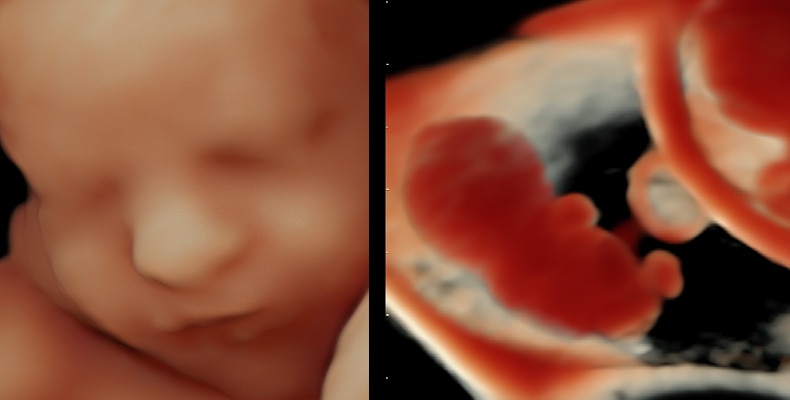

Nordic VISUS Basic

Course overview

Obstetricians, gynecologists, and midwives

Basic knowledge of obstetrics and/or gynecological 2D ultrasound